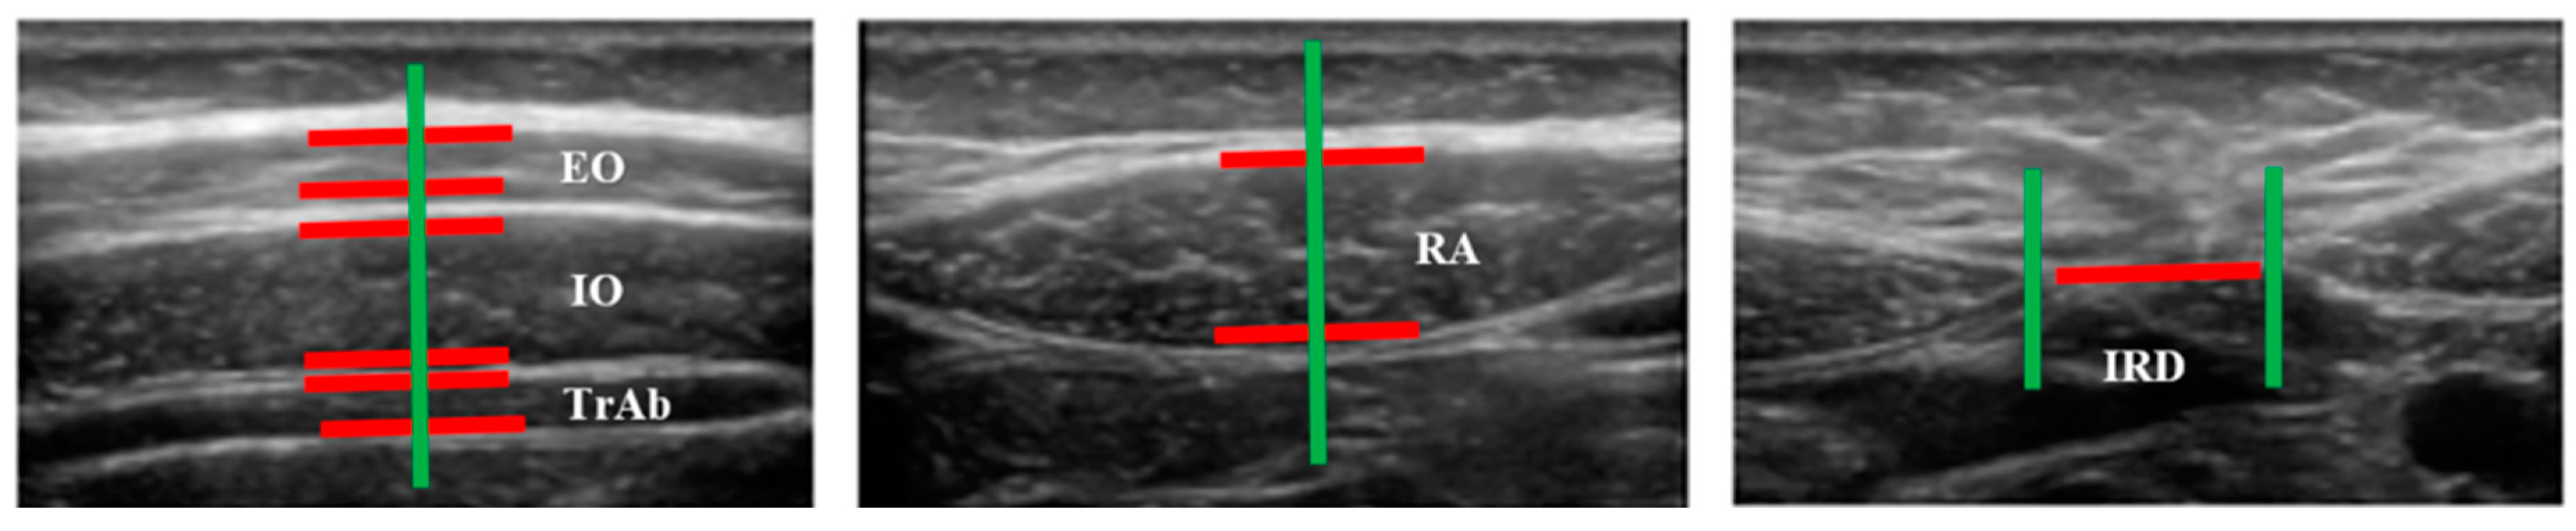

2.4. Outcome Measurements

| Measures | PD (n = 19) | Controls (n = 20) | p-Value |

|---|---|---|---|

| Distance (cm) IRD | 0.96 ± 0.48 (0.29–2.28) * | 1.26 ± 0.59 (0.54–2.58) * | 0.098 ** |

| Thickness (cm) | |||

| Right TrAb | 0.32 ± 0.74 (0.21–0.50) * | 0.34 ± 0.10 (0.18 –0.61) * | 0.428 ** |

| Right IO | 0.72 ± 0.14 (0.41–0.97) * | 0.71 ± 0.17 (0.41–1.09) * | 0.903 ** |

| Right OE | 0.48 ± 0.09 (0.29–0.60) * | 0.49 ± 0.11 (0.33–0.70) * | 0.557 ** |

| Left TrAb | 0.30 ± 0.06 (0.18–0.43) * | 0.32 ± 0.09 (0.20–0.57) * | 0.413 ** |

| Left IO | 0.72 ± 0.14 (0.46–0.94) * | 0.72 ± 0.17 (0.44–1.12) * | 0.939 ** |

| Left EO | 0.53 ± 0.79 (0.40–0.69) * | 0.52 ± 0.12 (0.34–0.81) * | 0.930 ** |

| Right RA | 1.02 ± 0.16 (0.67–1.22) * | 1.08 ± 0.21 (0.76–1.52) * | 0.341 ** |

| Left RA | 1.06 ± 0.13 (0.77–1.30) * | 1.07 ± 0.22 (0.78–1.54) * | 0.873 ** |